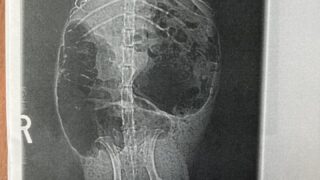

【体験談】モルモット(スキニーギニアピッグ)が突然食欲不振に…レントゲンで判明した原因と対処法

「昨日まで元気だったのに、急に食べなくなった…」我が家のモルモット(スキニーギニアピッグ)ぷり子も、ある日突然食欲が落ち、急いで動物病院へ行きました。この記事では、✔ 実際の症状✔ レントゲン結果✔ 自宅での対処法✔ 回復のためにやったこと...